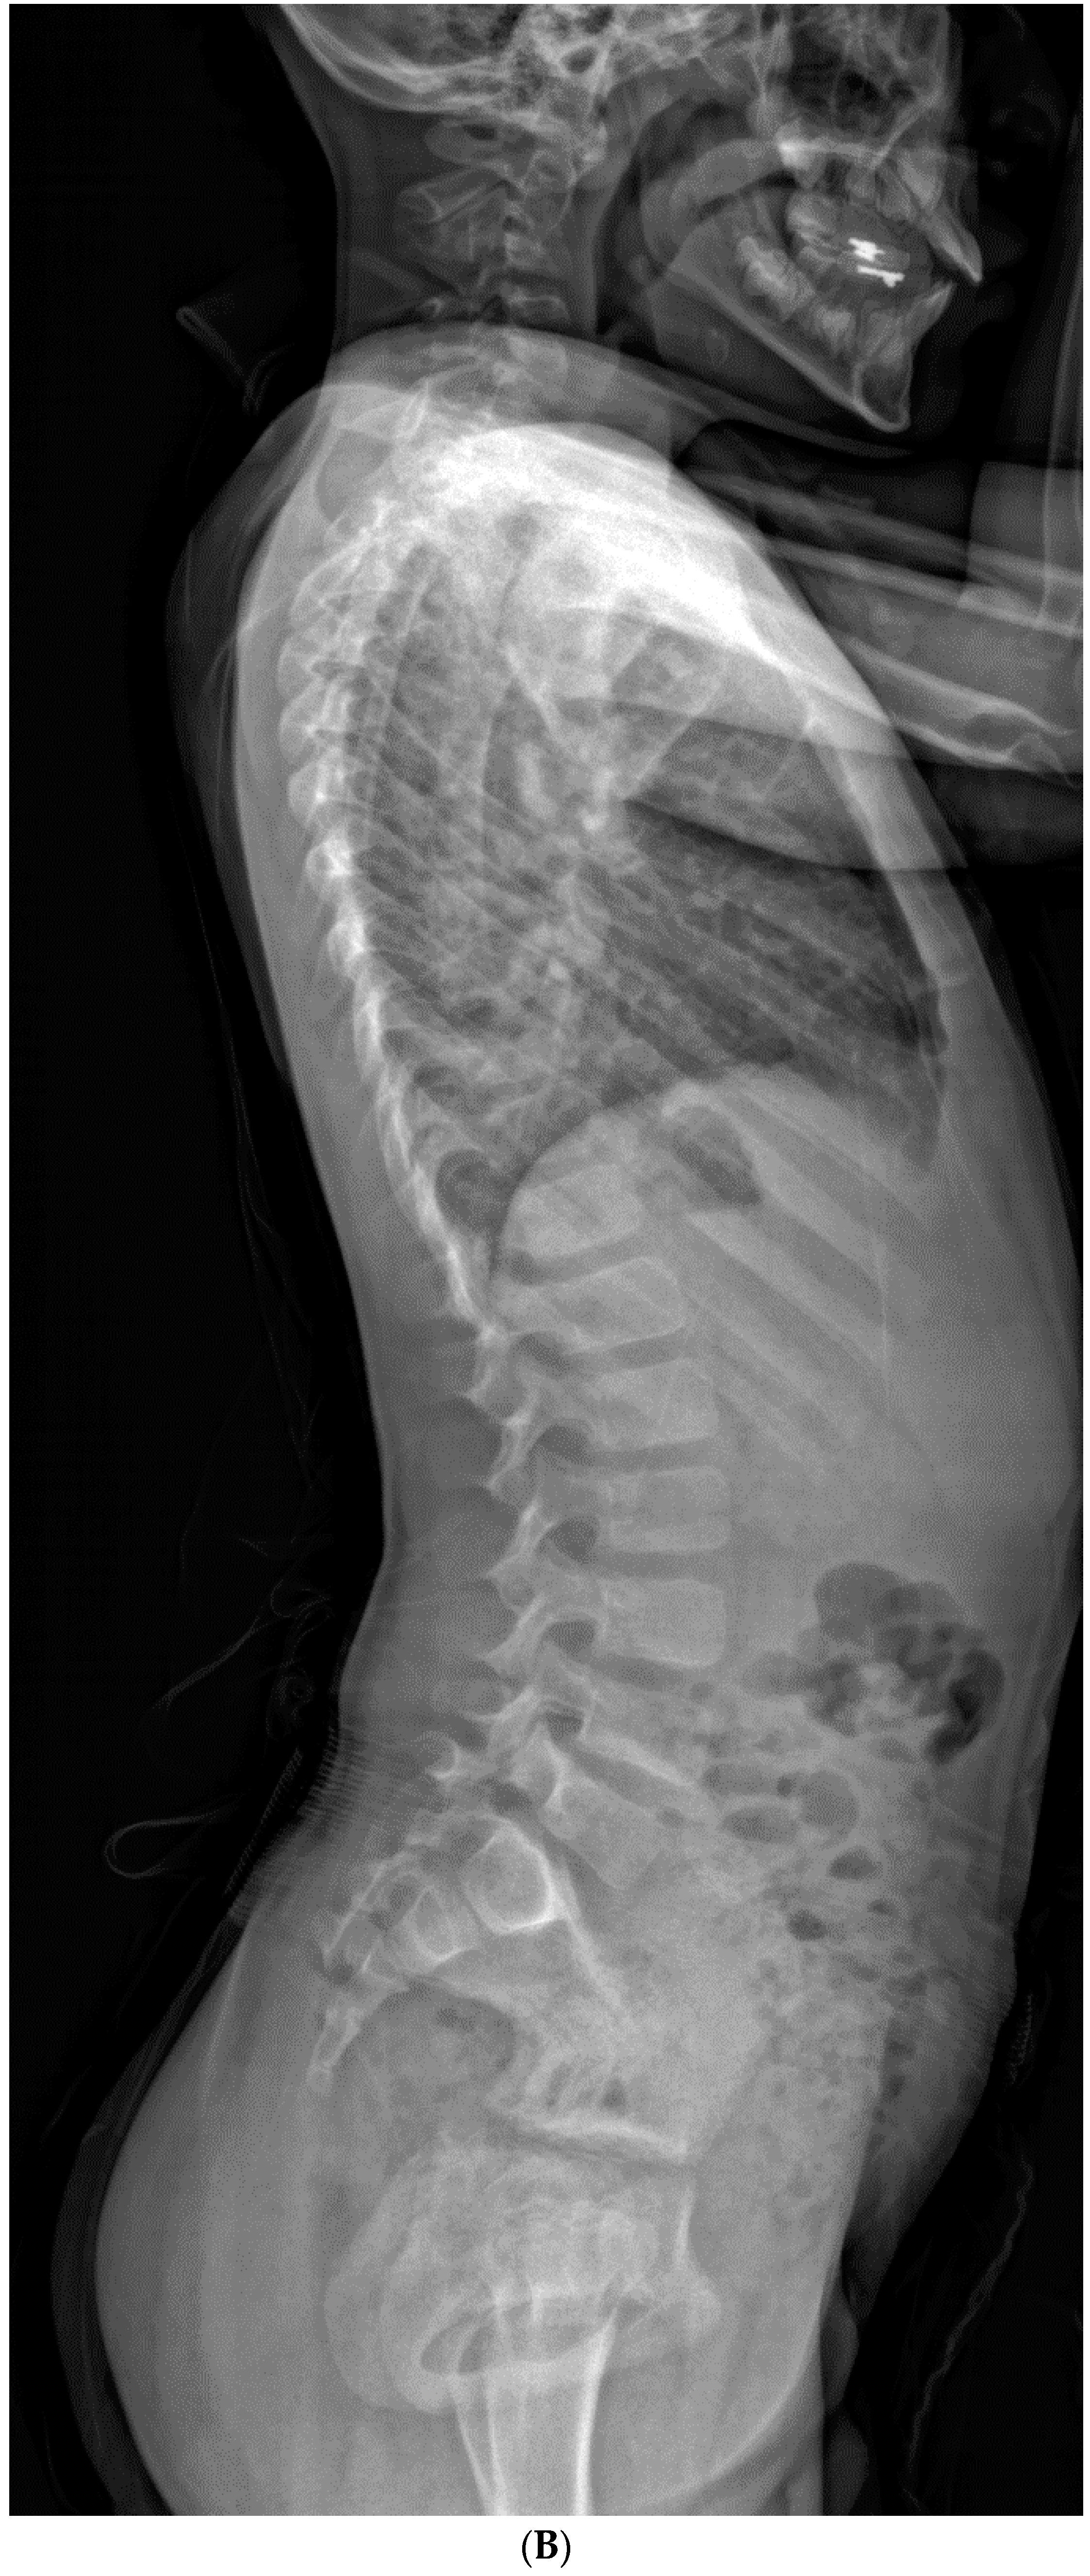

Figure 2.

(A–C). An 8-year-old boy diagnosed with CCS with progression of cervical deformity and compensatory curve. (A) PA radiograph shows a C7 hemivertebra. (B) Lateral radiograph. (C) Coronal CT highlights the left C7 hemivertebra. Patients with thoracic or lumbar vertebral anomalies (such as hemivertebrae, butterfly vertebrae, etc.) were excluded from this study. This was to best ensure that any compensation in the thoracic or lumbar regions was not due to vertebral anomalies in those regions.